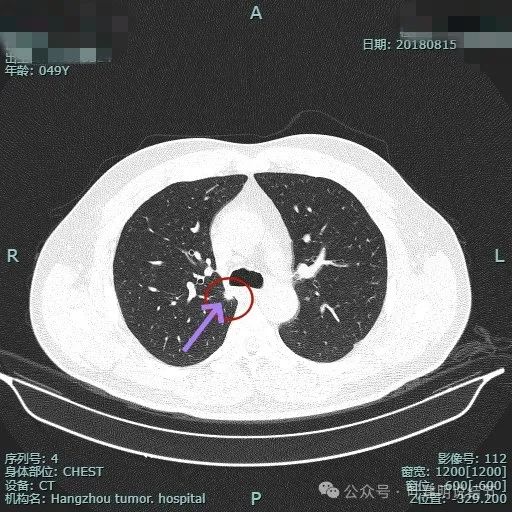

再看2018年时连续层面的:

病灶出现。

实性密度,边缘略糊。

表面毛刺。

紧贴胸膜。

血管进入。

整体轮廓较清。

细毛刺明显。

缺乏膨胀性。

边缘区密度较淡。